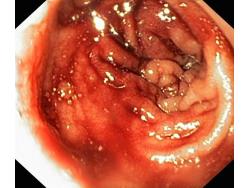

Krwawienie